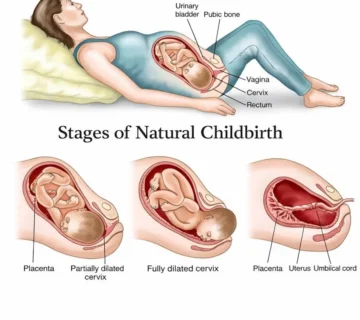

Heart Formation and Beating

One of the most important events of the fifth weeks is the beginning of the development of the fetal heart. At this time, the heart is still a small, simple tube, but its cells are starting to beat and the initial blood flow is moving through the fetus’s body.

In the coming weeks, this simple tube will divide into two ventricles, the left and right, and the fetal heartbeat will be visible and audible with a vaginal ultrasound.